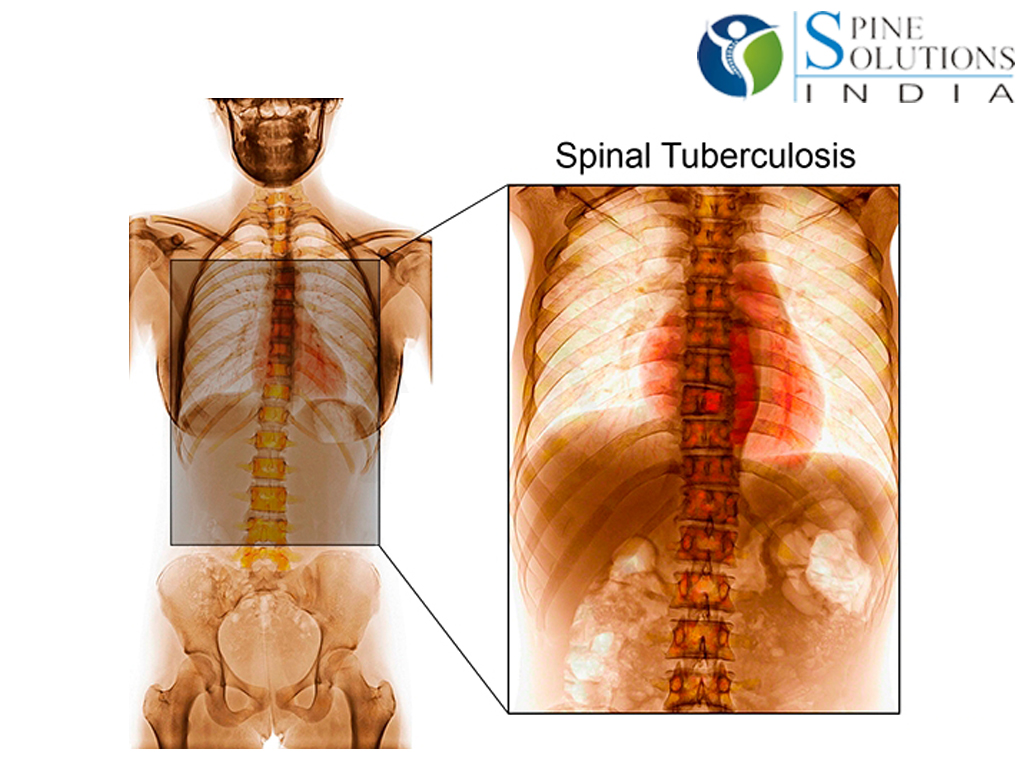

Медицинские аспекты заболеваний: рентгенологическая картина туберкулеза костей

Раздел: Снимки-откровения